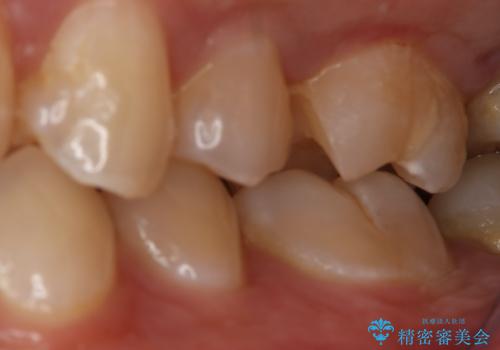

- 左上6番の銀歯のやり変えを希望し来院された患者様です。

切削量・形態を考慮し、セラミックインレーでの治療を計画しました。

銀歯直下のう蝕が深かったのでCRで裏層した上で形成、印象をしています。